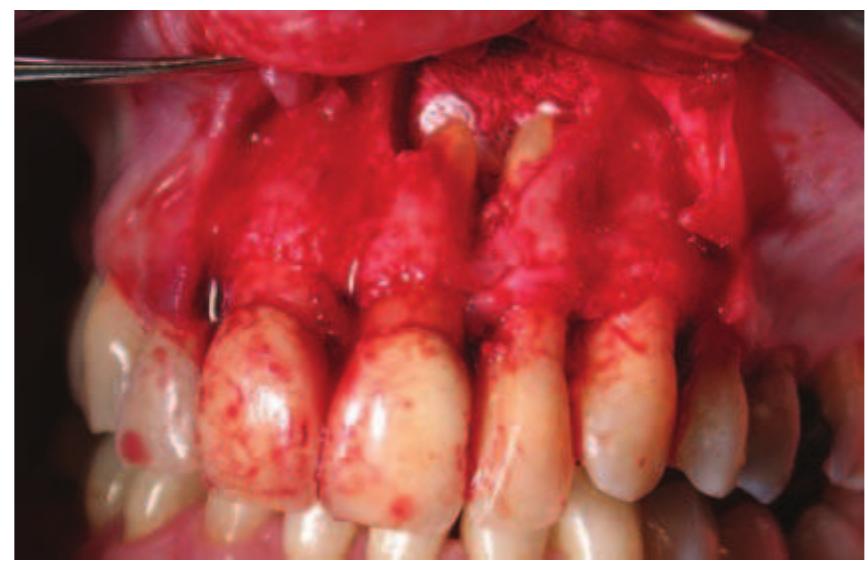

- Perhaps the root canal treatment was carried out while the teeth were still vital and the root canals were not infected.

- In the majority of cases, root end surgery would not be carried out unless the root canal had been thoroughly cleaned prior to treatment.